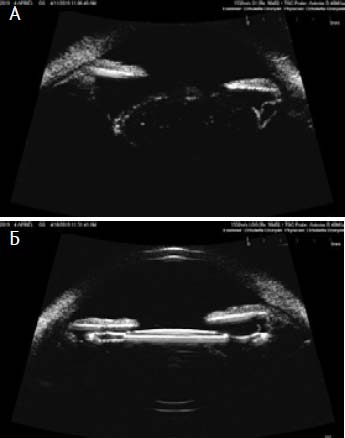

По данным ультразвуковой биомикроскопии ИОЛ во всех случаях была фиксирована и находилась в центральном положении (рис. 2).

Рис. 2. А. Ультразвуковая биомикроскопия. Сканограмма подвывиха хрусталика 2-й степени пациента Б. 54 лет до оперативного лечения катаракты. Б. Тот же пациент после одномоментной верхней фиксации моноблочных интраокулярных линз к радужной оболочке в ходе факоэмульсификации катаракты с сублюксацией хрусталика